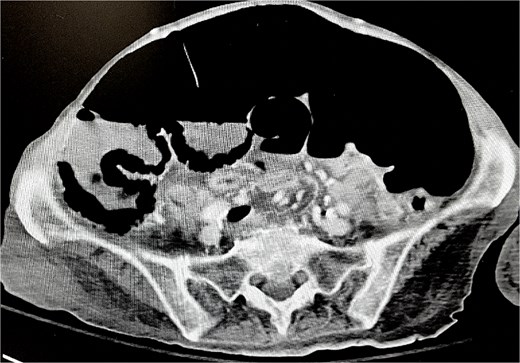

Soon thereafter, a large prolapse of the cecostomy site was noted (Figs 2 and 3). Conservative measures including manual reduction and hyperosmotic agents were unsuccessful. On April 15, 2025, she was taken to the operating room. Diagnostic laparoscopy revealed a small fascial defect at the cecostomy site with cecal intussusception. The fascial defect was extended cephalad, and the prolapsed cecum was successfully everted and reduced (Fig. 4). Due to the chronically dilated right colon and the patient’s history of refractory ACPO, a right hemicolectomy with end-ileostomy was performed.

Anterior/posterior view of incarcerated cecostomy intussusception.